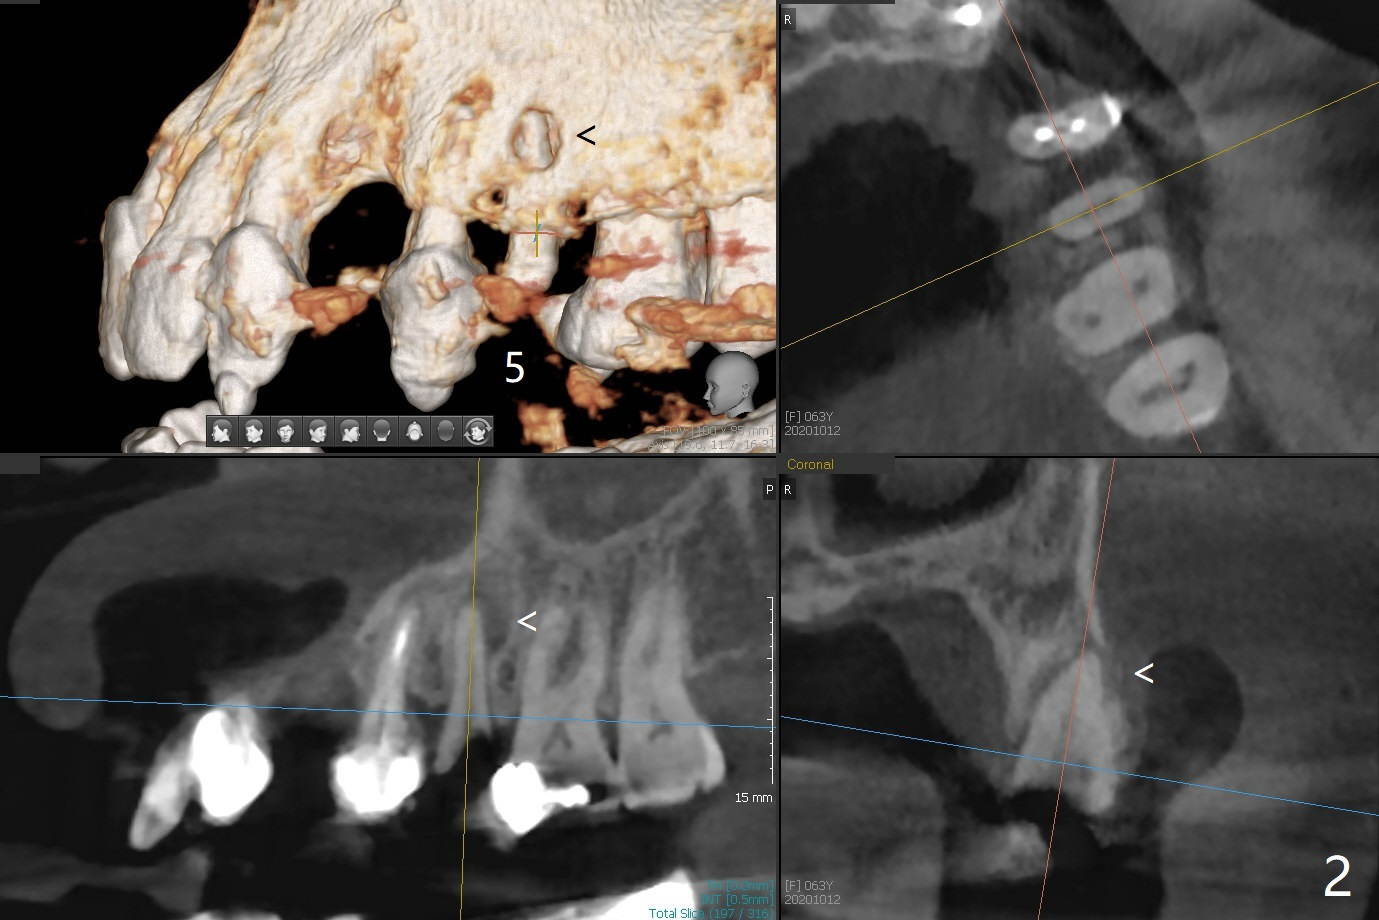

63岁女需要四个植牙(图一:左上3,5,右下6,7),由于3牙槽嵴狭窄,选择导板种植。5根尖阴影,颊侧骨板穿孔(图二:箭头)。即种时如何修复?骨粉,植体,哪个先放